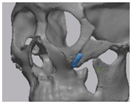

2.2. Computer-Aided Virtual Surgery, Design, and Fabrication of Patient-Specific Devices

2.5. Cone Beam CT and 3D Comparison